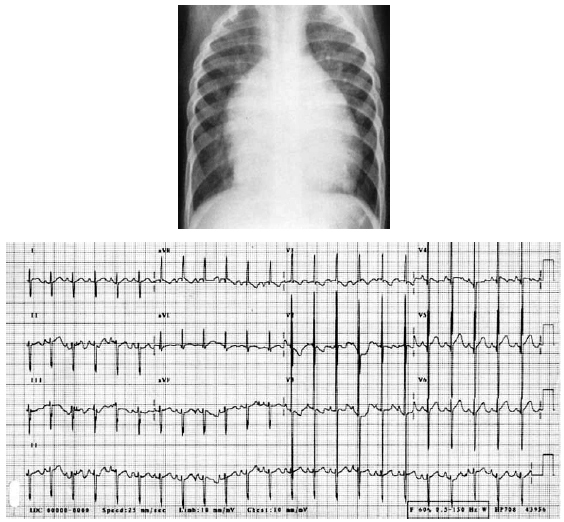

Paciente é encaminhado por sopro cardíaco e apresenta os seguintes exames complementares:

O diagnóstico mais provável é: